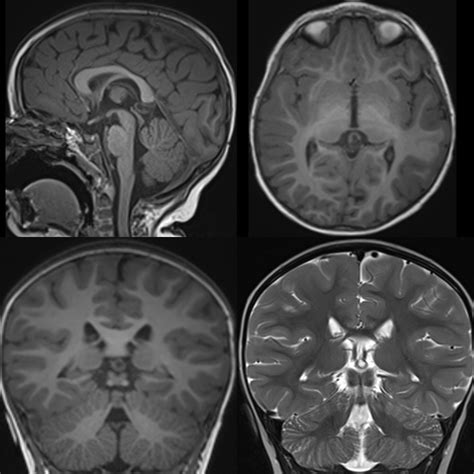

Diagnosing and Monitoring

In most instances, a Pineal Gland Cyst is discovered incidentally. Once identified, neuroradiologists evaluate the cyst using magnetic resonance imaging (MRI). The imaging helps determine the size, appearance, and whether the cyst is putting pressure on critical brain structures.

Appearance Smooth, thin-walled, and fluid-filled.

Growth Typically stable; they rarely grow or change over time.

• pineal gland cyst mri

• pineal gland cyst radiology